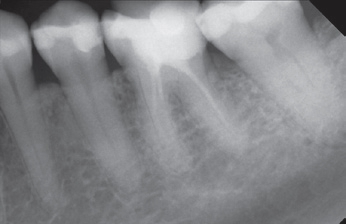

Eine 52-jährige Patientin wurde vom Hauszahnarzt mit der Bitte überwiesen, vor geplanter prothetischer Versorgung eine endodontische Revisionstherapie am Zahn 36 durchzuführen (Abb. 1). Der Zahn reagierte auf die Sensibilitätsprüfung mit CO2-Schnee negativ, auf Perkussion stark positiv. Die endodontische Diagnose lautete: Pulpastatus: pulpless and infected; periapikaler Status: symptomatic apical periodontitis.